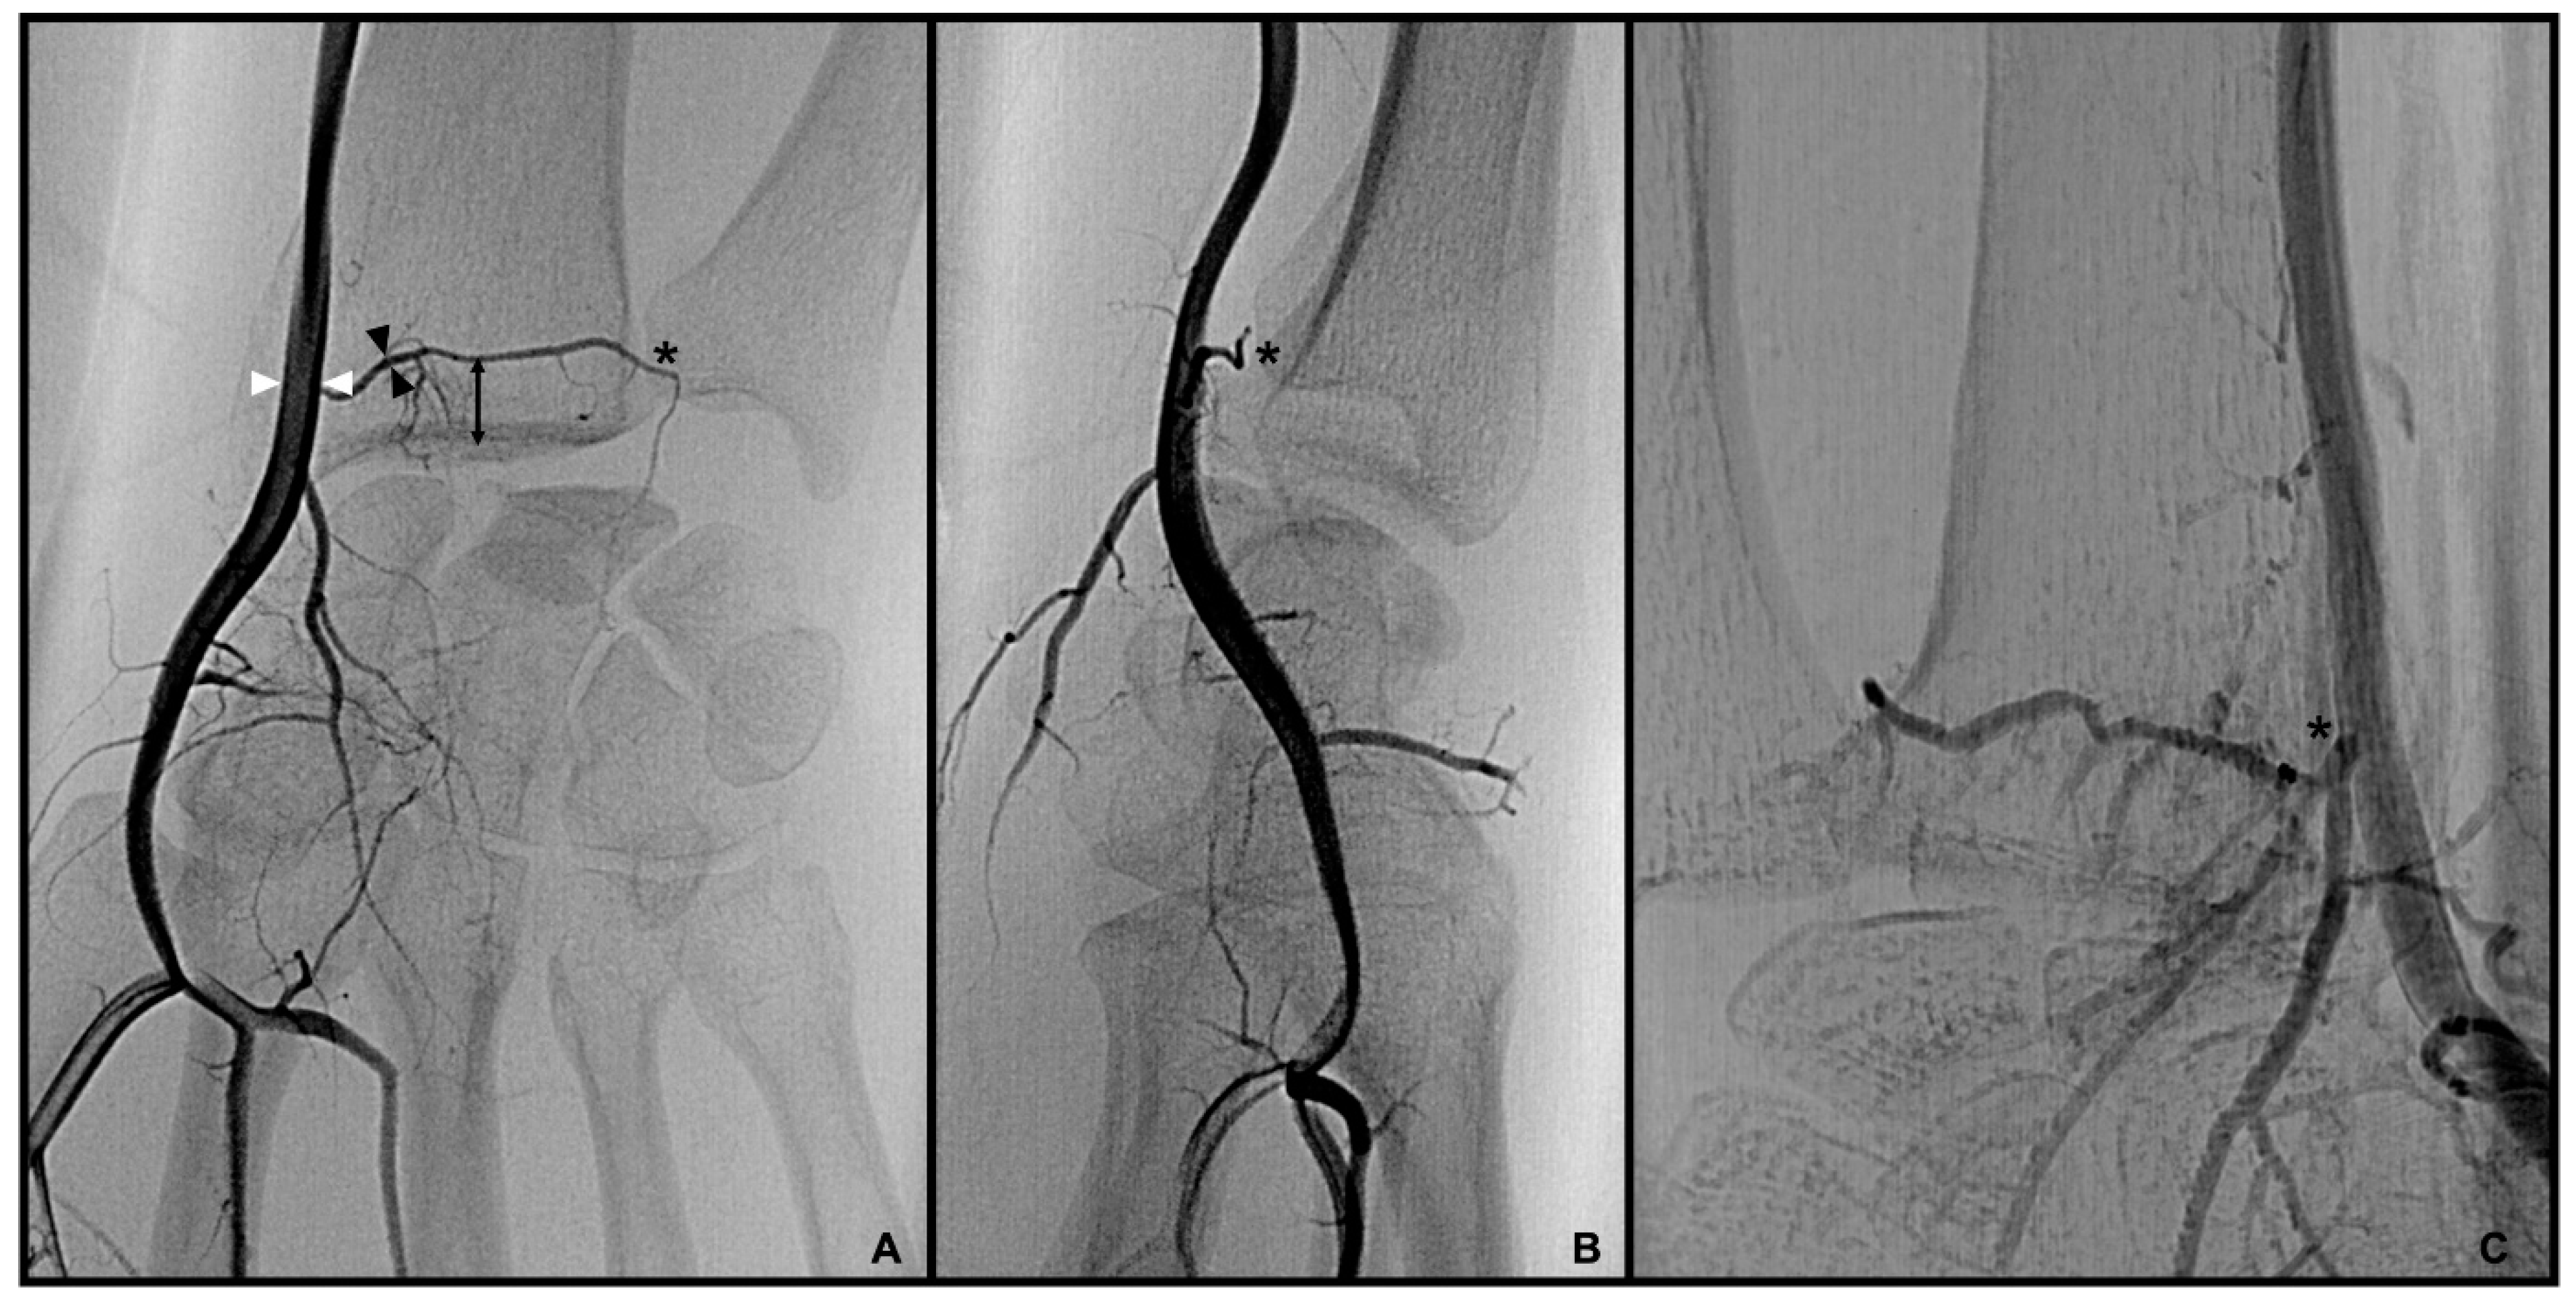

3.1. Palmar Radiocarpal Artery and Palmar Radiocarpal Arch (PRCA)

3.2. Dorsal Carpal Branch of the Ulnar Artery (DCBUA)

3.3. Anterior Interosseous Artery (AIA)

distance from the DCBUA to the styloid process of the ulnar (DCBUA = dorsal carpal branch of the ulnar artery).